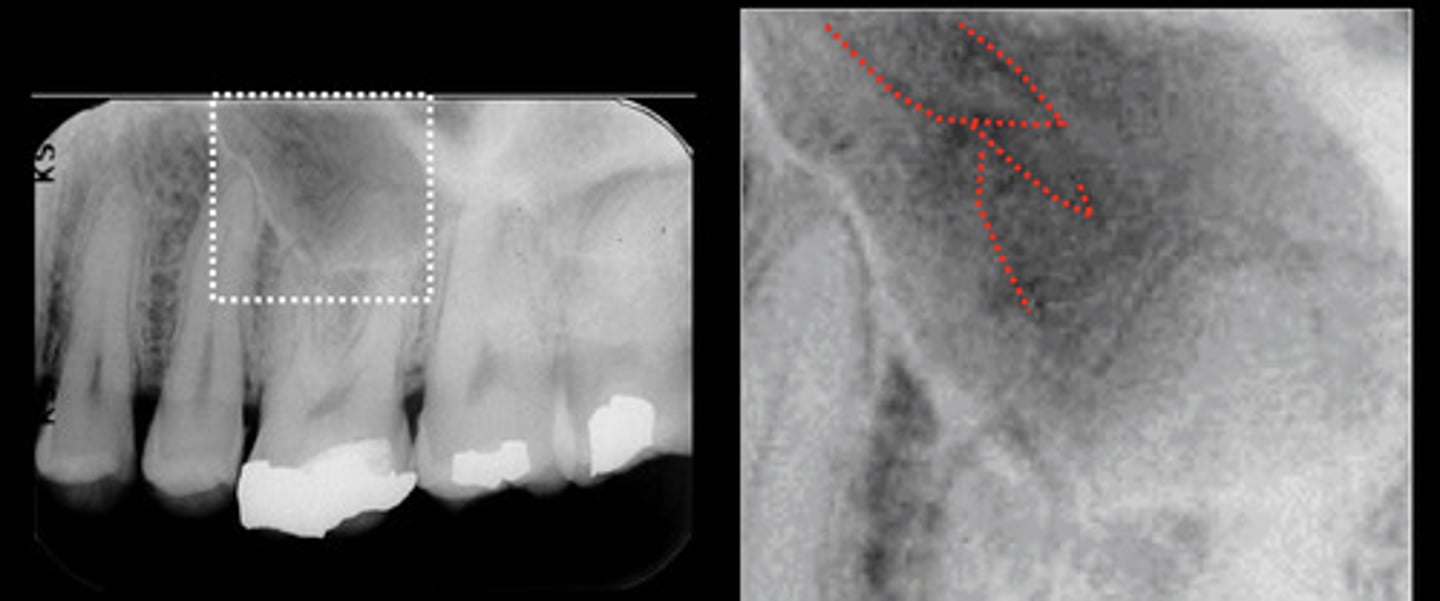

What are the red arrows representing?

Pulp chamber and root canals